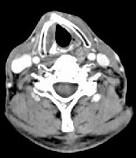

问题 男,63岁,咽喉部不适约1年,近2个月经常咳嗽,痰中带有血丝,CT如图所示,应诊断为()

选项 A.梨状窝癌 B.声门型喉癌 C.声门下型喉癌 D.声门上型喉癌 E.混合型喉癌

答案 D